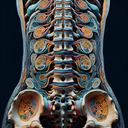

МРТ

Магнітно-резонансна томографія (МРТ) — це сучасний та безпечний метод діагностики, що дозволяє отримати детальні зображення внутрішніх органів і тканин. Він базується на використанні сильного магнітного поля та радіохвиль. **Переваги МРТ:** 1...